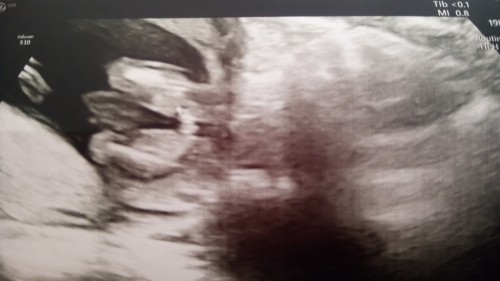

Ya arkadaşlar bugün bu üçüncü postum sanırım. İlkinde ikili test için açtım sabah. Doktorum gereksiz yere beni korkuttu. Sabah başıma resmen ağrı saplandı. Neyse, sonra bebişin cinsiyetini söyleyecekti, bebek kocaman açtı bacağını ama doktor bi kız dedi,bi erkek dedi. Bence kız. Net görünüyor yani.

16 haftalık oldum. Artık net görünüyor herşeyi bebişin. Ben kıza göre yarın  biraz alışveriş yapayım diyorum. Deşarj olmaya ihtiyacım var. Doktor bir arkadaşım var ona da sordum gösterdim ultrasonu o da kız bence dedi. Sizce alışveriş yapayım mı? Kız denilip oğlu olan yada tam tersi olan oldu mu aranızda?

Kız bu daha tam oluşmamış gibi geldi bana ne kadar anlayabilirimki ☺☺☺☺☺☺☺☺☺

Sanki bu daha kıza benziyo benim ultrasona göre

Çıkıntısı yok demi